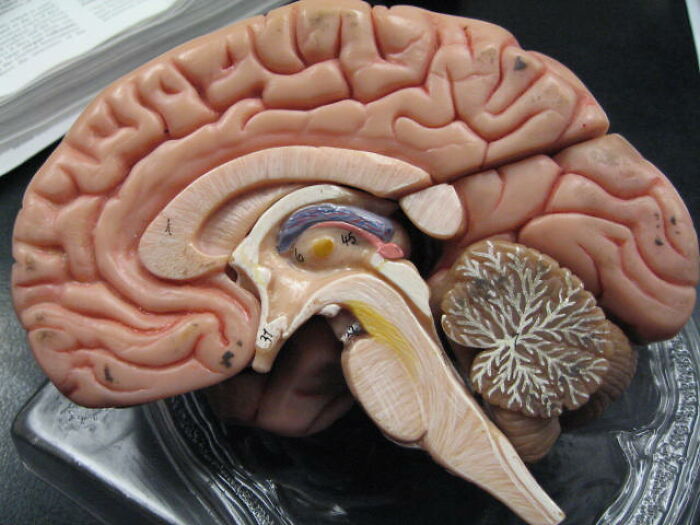

That one misfolded protein can wind up rendering a brain about as useful as rotting cheese.